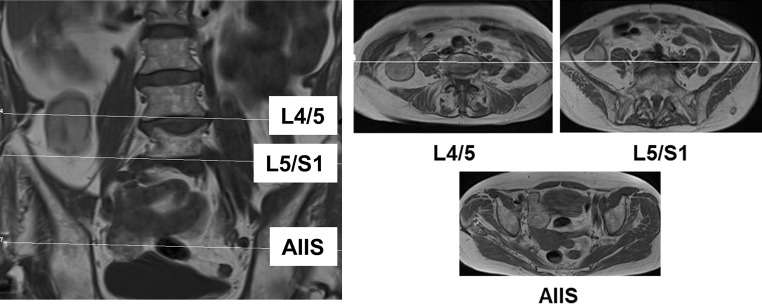

More than 6 months postoperatively (median 456 days, range 196–842 days), 18 of the 20 patients (one refused due to claustrophobia, one had a pacemaker which was not suitable for MRI) underwent MR imaging of the hip region for the assessment of muscle quality of the hip flexor muscles (M. iliacus, M. psoas major, M. iliopsoas) as previously described using the four-tiered classification established by Goutallier et al. [12, 13]. All MRI examinations were performed on both the operated and the contralateral side by two experienced radiologists, giving a total of 120 measurements. The fatty infiltration of individual muscles was assessed according to the classification system proposed by Kaniewska et al. (anatomy-based MRI assessment of the iliopsoas muscle complex after petrochanteric femoral fracture, under revision, March 2018). The intervertebral discs at L4/L5 and L5/S1 were used as radiological landmarks for the iliacus and psoas major, respectively, while the anterior inferior iliac spine was used as a landmark for the iliopsoas (Fig. 1). In addition, the mean global fatty degeneration index (GFDI) was calculated for each muscle as previously described for rotator cuff lesions [12, 13].

Fig. 1.

Anatomical landmarks used in MRI-based assessment of fatty infiltration. MRI magnetic resonance imaging; L4/5 lumbar segments 4/5; L5/S1 lumbosacral segment; AIIS anterior inferior iliac spine